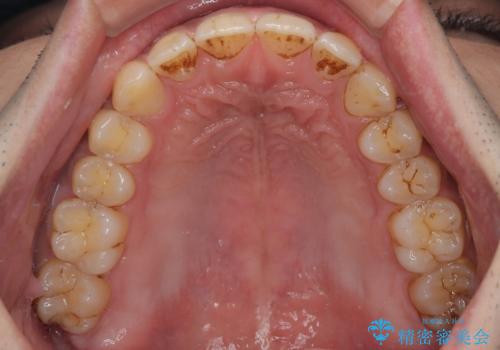

- 上の前歯の正中離開(すきっ歯)と、下顎前歯部の叢生(デコボコ)を主訴に来院された患者様の症例です。

正中離開は舌の癖(舌突出癖)がある場合、後戻りしやすい傾向があります。

そのため当院では矯正治療と並行して、正しい舌の位置・飲み込み方・呼吸の仕方などをトレーニングする

**MFT(口腔筋機能療法)**を実施し、治療後の安定性を高めています。